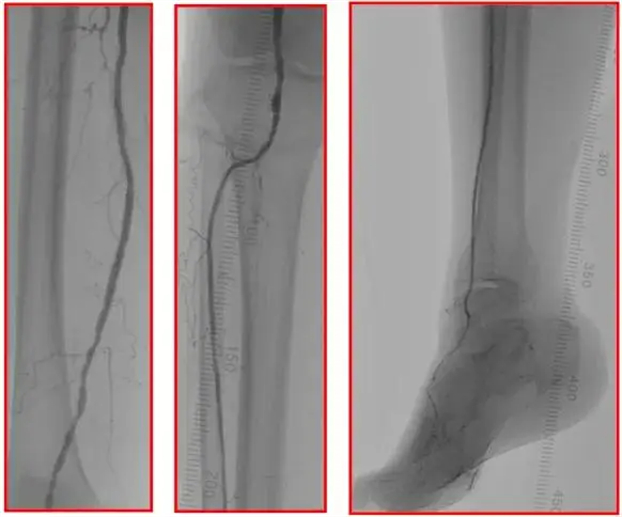

术后造影

本例患者为严重下肢动脉缺血,术中导丝顺利真腔通过闭塞段血管,应普通球囊成形效果欠佳,使用外周血管内冲击波球囊扩张后得到满意的管腔获得。后续应用药物涂层球囊治疗,以获得良好的远期通畅率。患者术后右足破溃疼痛明显减轻,双下肢皮温回暖。